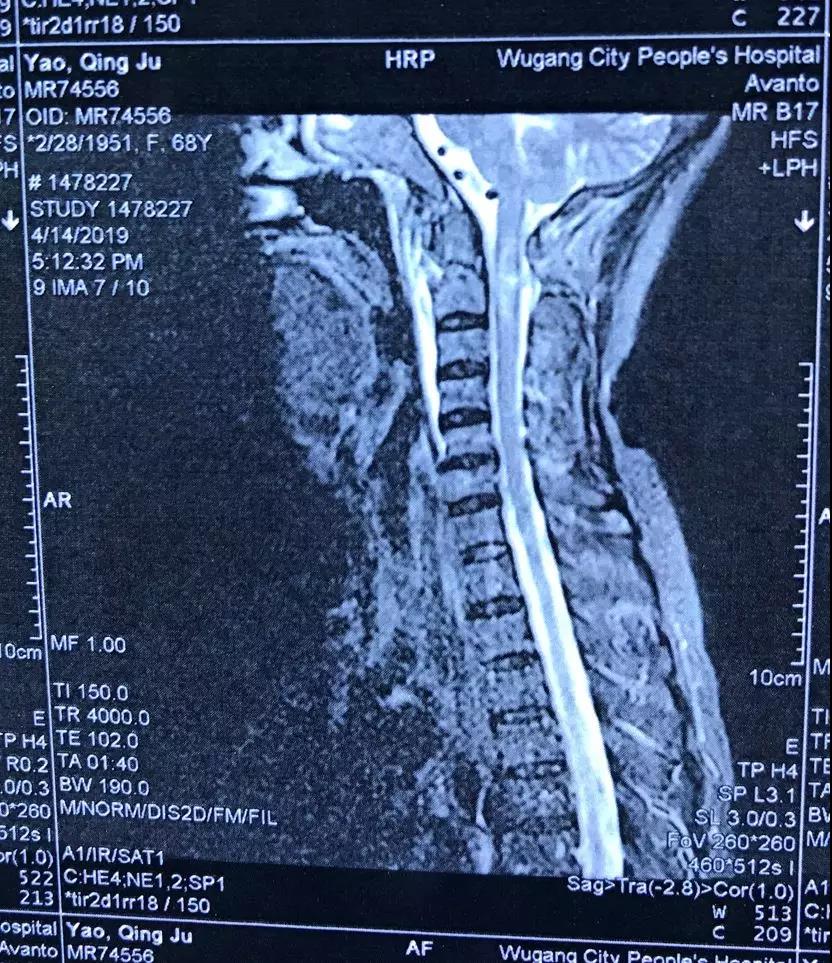

骨卫士特聘专家、原解放军307医院范海涛主任在会上分享了一例C2枢椎齿状突骨折并颈髓挫伤患者病例 。患者为67岁女性,因摔伤致四肢麻木,不能活动。

患者影像资料如下:

▲术前MRI